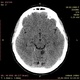

Мало того в левом полушарии мозжечка - гиподенсивный округлый участок без объемного воздействия. Плотность не ликворная. Киста? Образование?

![]()

Уважаемый, Коллега! Разрешите Вас поправить: исследование не ушей, а височных костей. В отношении Лор-патологии А.Ю. коротко Вам написал. Но после Вашего исследования, для пациента наиболее важным становится анализ кистоподобного образования мозжечка, которое в диф. диагностике может быть: от кисты - до онкологии. И теперь для Вас, как для врача лучевой диагностики стоит задача возможными методиками или др. методом определить характер пат. зоны. Либо КТ, либо МРТ с внутривенным контрастированием.